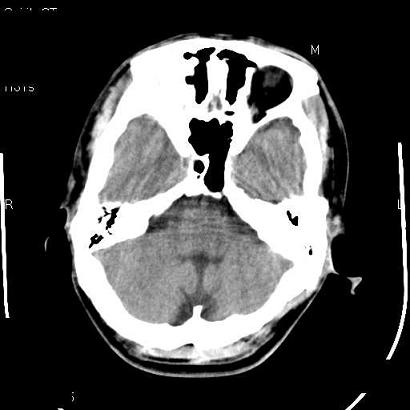

男,39岁,外伤来诊,老师们看看枕骨是什么病

蛛网膜颗粒压迹特点:位于中线两侧的颅骨圆形或类圆形低密度影,常多发,可融合,边缘有硬化缘,无软组织肿块。

枕内隆突左缘板障区示不规则囊状透亮区,颅骨内外板规整,无膨胀及缺损,周围无软组织肿块,考虑板障血管性病变,1.板障静脉湖,2.枕骨血管瘤(局部无膨胀性改变,无硬化环及钙斑影,故不太支持)。